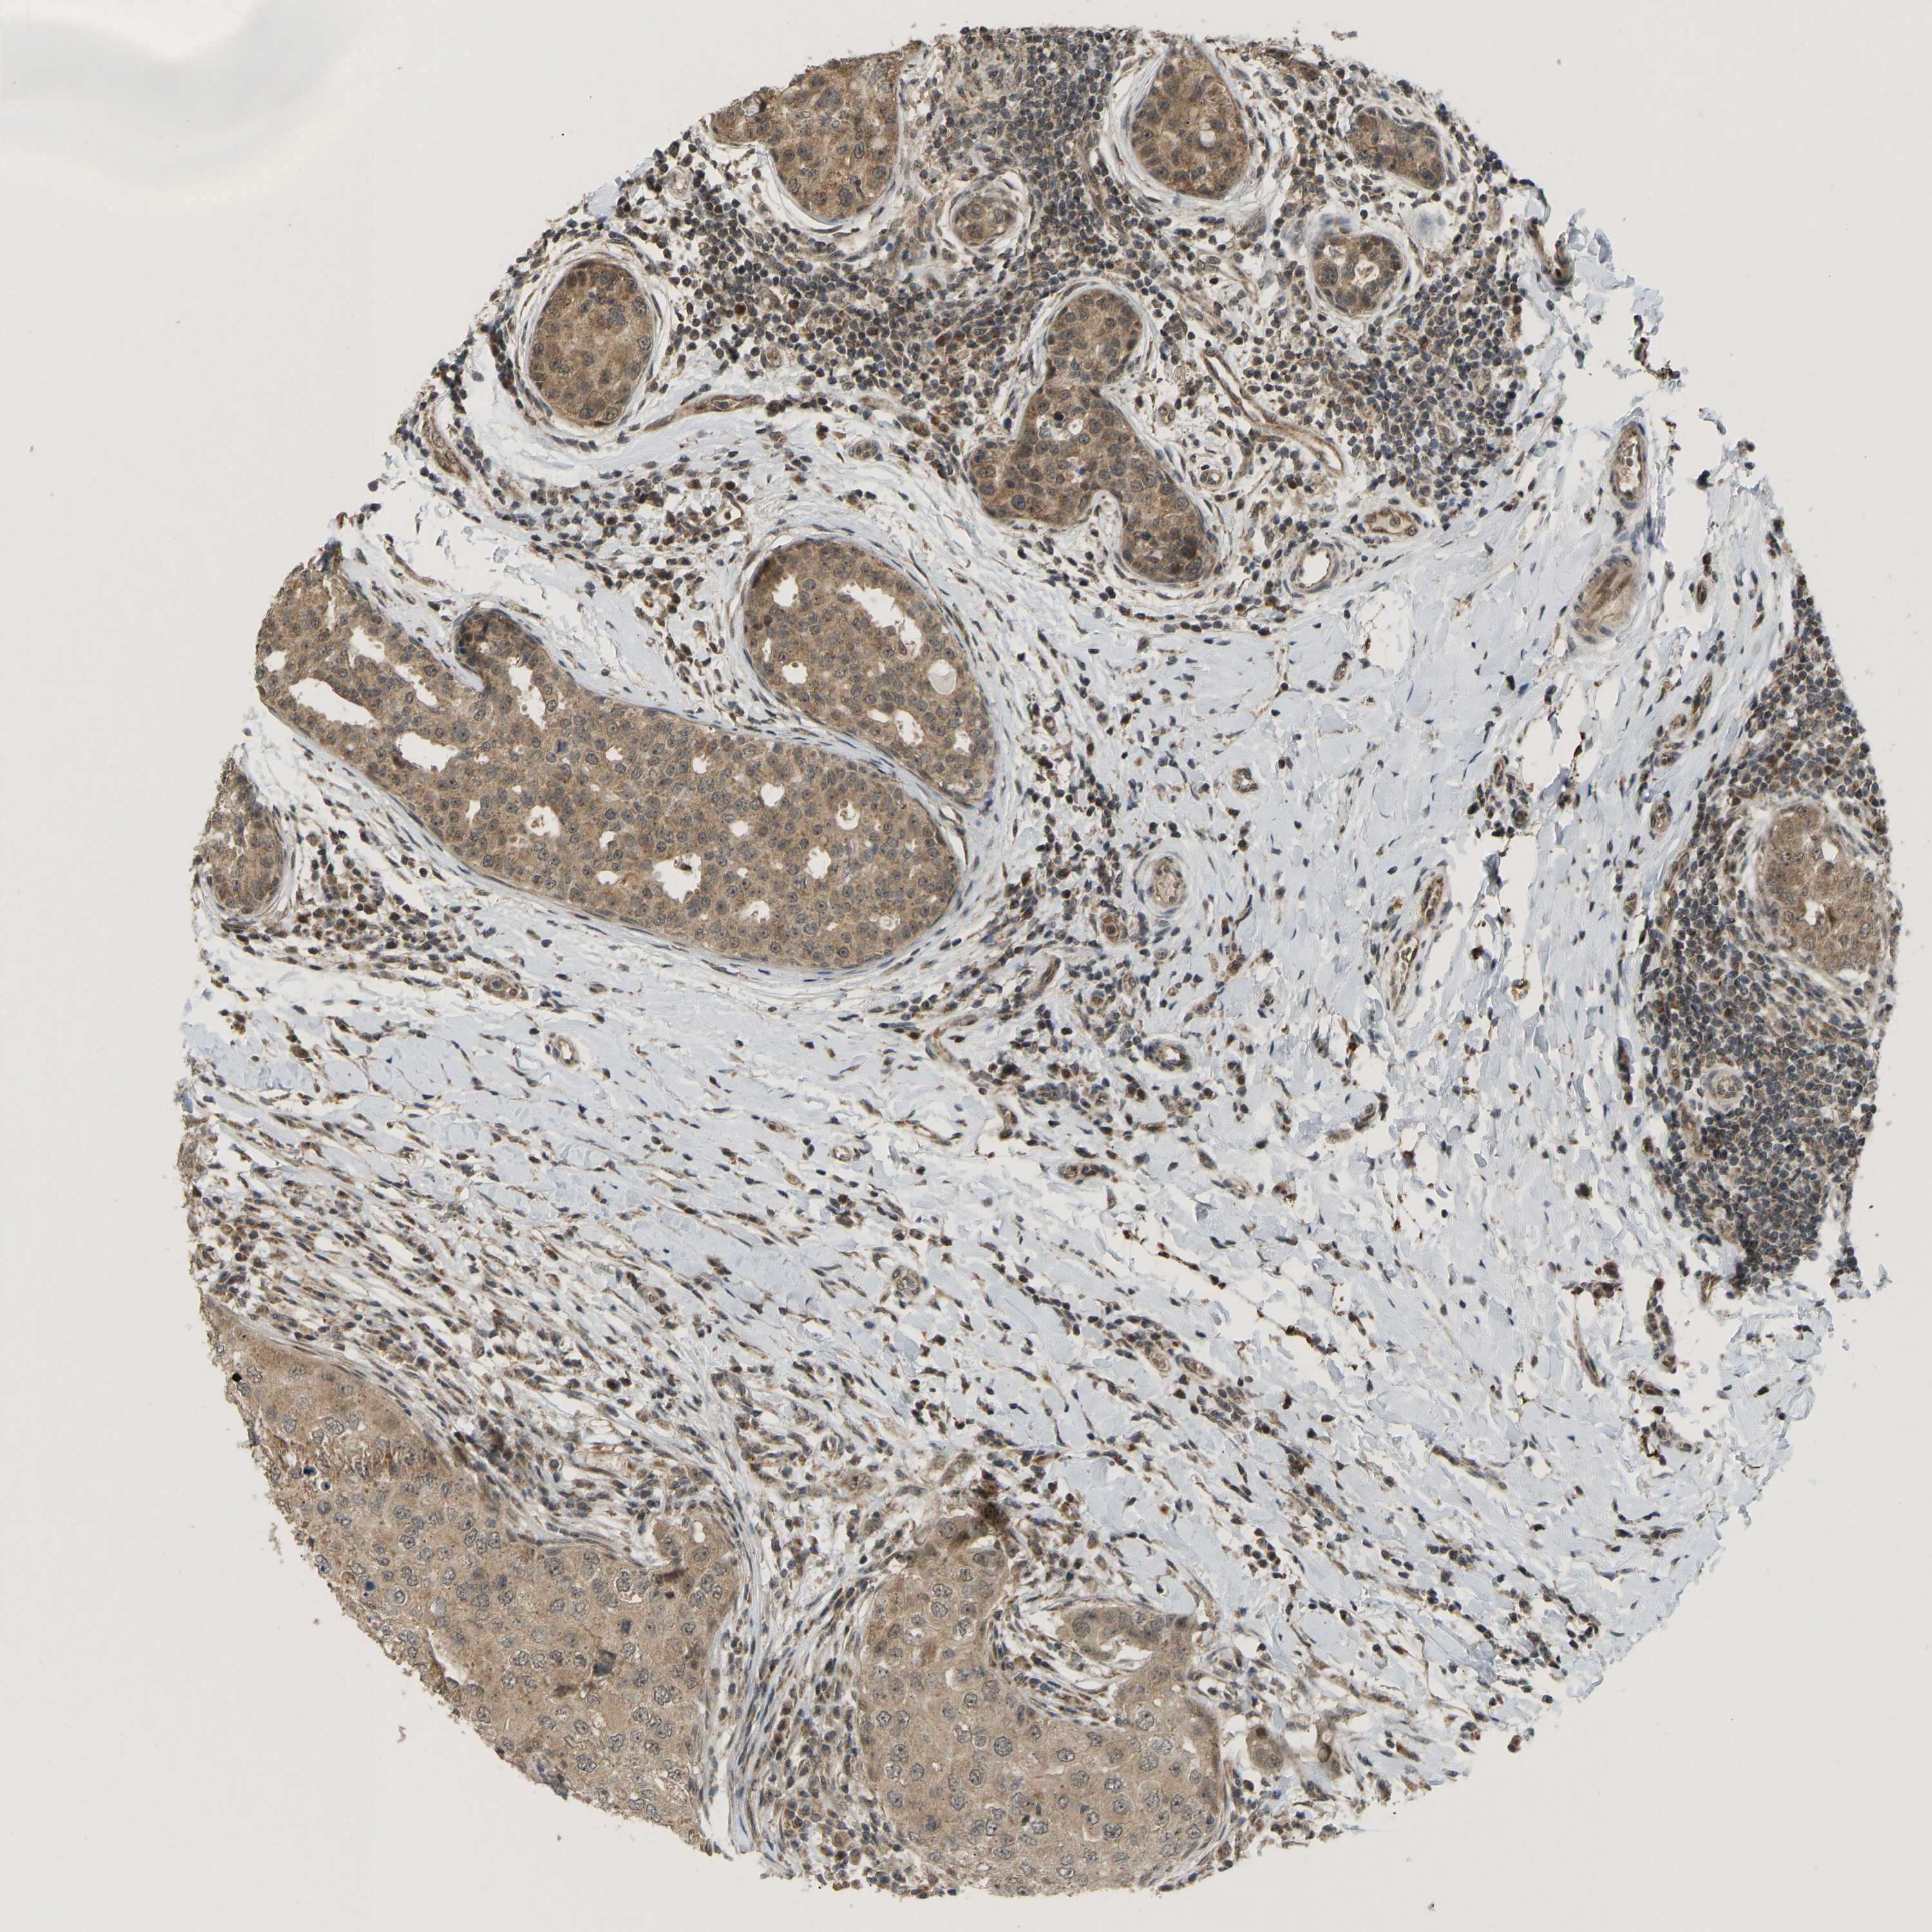

BRCA TCGA BRCA VALIDATION PROTEIN EXPRESSION

ANTIBODIES

AND

VALIDATION